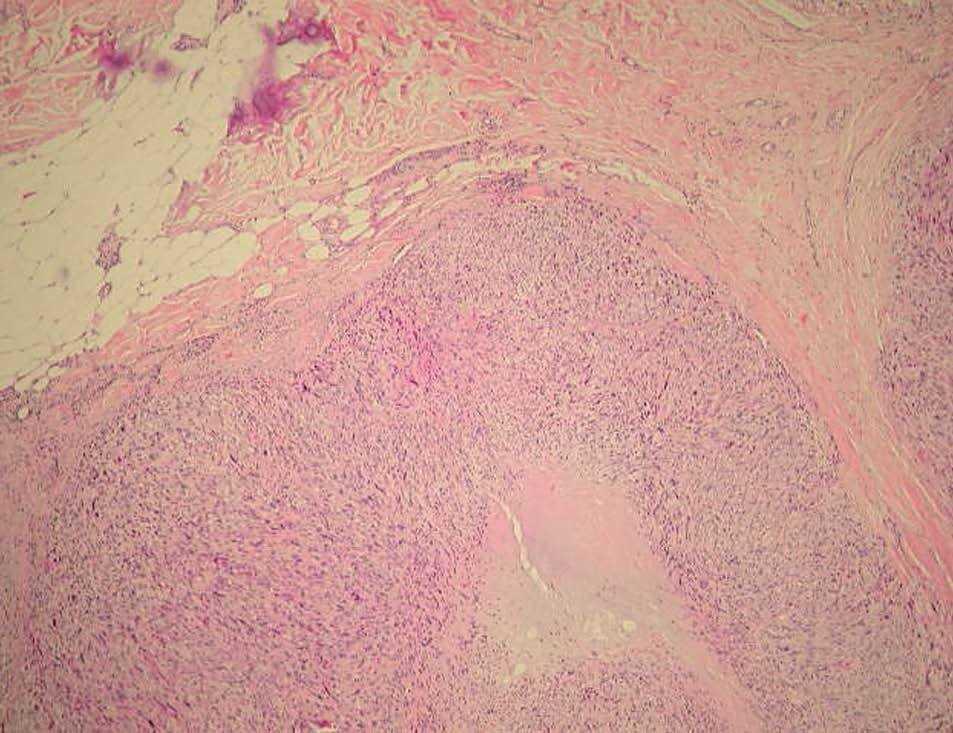

Fig. 2.--Neoformación de células fusiformes, bien circunscrita, de patrón nodular y ubicada en dermis (media y profunda) e hipodermis (Hematoxilina-eosina, x10.)

Se observó una neoformación de estirpe mesenquimatosa, bien circunscrita, de patrón nodular y ubicada en dermis (media y profunda) e hipodermis (fig. 2), conformada por celularidad de morfología fusiforme dispuesta en fascículos interconectados y con focos verticilados, que contorneaban zonas de necrosis geográfica central. La celularidad neoplásica mostraba núcleos cariomegálicos e hipercrómicos, de extremo romo y puntiagudo en el polo opuesto, con elevada actividad mitótica e inmunorreactividad frente a vimentina (fig. 3) y actina específica de músculo liso (fig. 4) y negatividad para el resto de marcadores testados (desmina, CAM 5.2, S100, CD68, EMA, CD34).